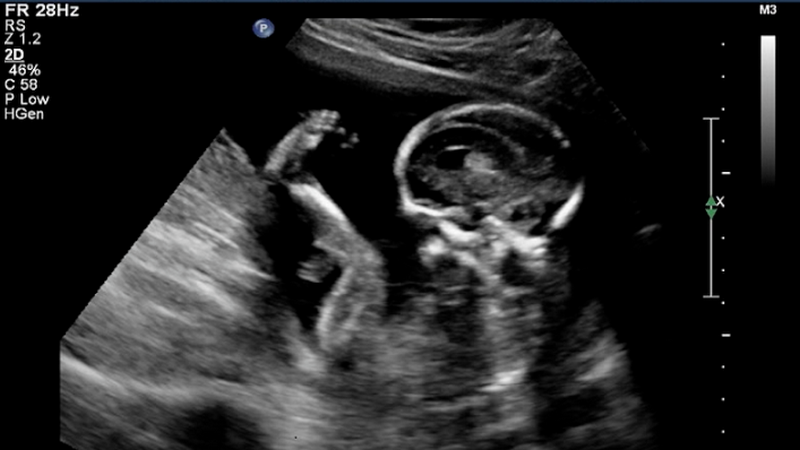

Siêu âm là một kỹ thuật chẩn đoán hình ảnh không xâm lấn hiện được sử dụng rất phổ biến trong y học. Nguyên tắc là đầu dò của máy sẽ gửi sóng siêu âm tần số cao hơn tần số mà con người có thể nghe được vào cơ thể. Khi sóng âm chạm vào các mô bên trong cơ thể phản xạ sẽ được đầu dò này thu lại truyền đến máy phân tích và cho ra hình ảnh.

Các loại mô khác nhau sẽ có khả năng hấp thụ và phản xạ siêu âm khác nhau nên sóng âm thu về cũng ở các mức độ khác nhau. Điều này giúp máy tính dễ dàng phân tích tiếng vang phản hồi và tái tạo lại hình ảnh lên màn hình, tạo ra những hình ảnh khác nhau về cấu trúc cơ thể.

Siêu âm 2D là phương pháp được dùng nhiều nhất để siêu âm thai và khám thai định kỳ. Vì là phương pháp siêu âm được phát minh đầu tiên nên hình ảnh thu được là hình đen trắng và chỉ có thể quan sát được một ít cử động của thai nhi. Mặc dù vậy nhưng các bác sĩ và mẹ bầu vẫn có thể theo dõi sự phát triển của bé trong suốt thai kỳ.

Siêu âm 2D thường được sử dụng trong những tháng đầu của thai kỳ để kiểm tra vị trí, tình trạng của thai nhi trong hay ngoài tử cung, các dấu hiệu bất thường như sứt môi và hở hàm ếch,... Siêu âm 2D được chia thành các loại sau: